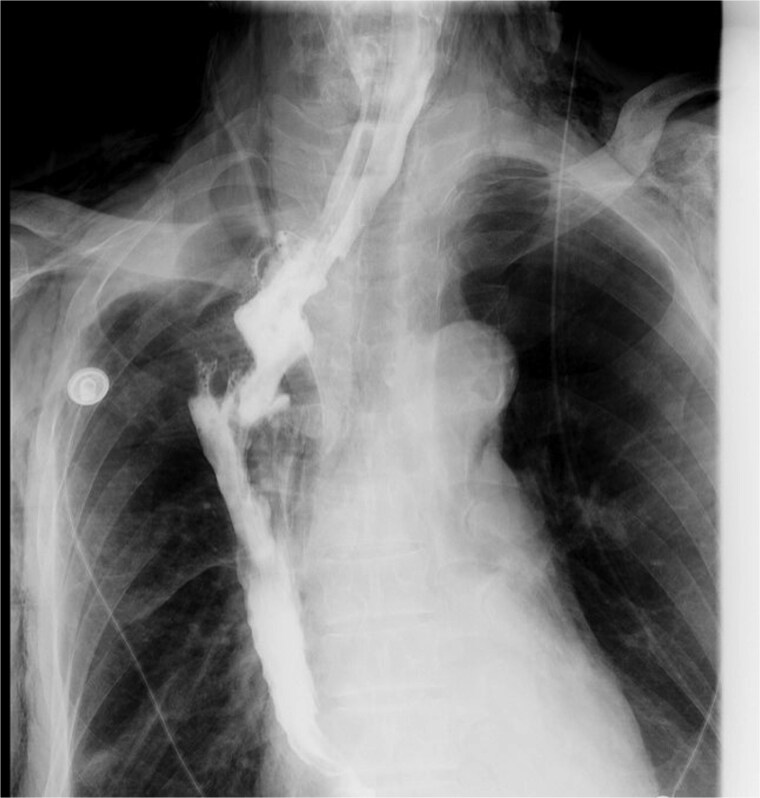

Esophagogastric anastomotic fistula is a common complication following esophageal cancer surgery, typically occurring within the first postoperative week. Conventional management requires prolonged fasting until complete fistula closure, which significantly impacts patient quality of life. We present a case of a male who developed an esophagogastric anastomotic fistula 2 months postoperatively, complicated by a concurrent gastrobronchial fistula. Endoscopic evaluation revealed persistent gastric wall defects at the fistula site. As the disease progressed, thickened visceral pleura formed dense adhesions with the damaged gastric tissue, effectively sealing the defect and preventing digestive fluid leakage into the thoracic cavity. By promptly promoting gastric emptying and reducing gastric acid secretion, the patient resumed oral intake without developing severe infections or complications.